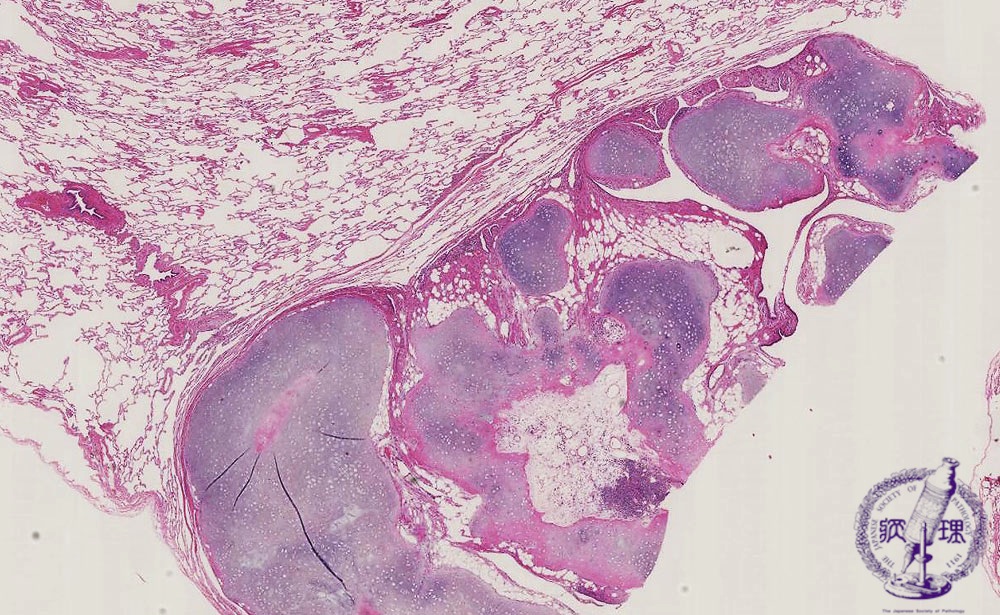

- (15)Hamartoma

Microscopic view (HE stain, low power view): The tumor is well-demarcated and composed of cartilage, adipose tissue and bronchial epithelium, all of which are normal bronchus components; however, the elements lack any normal organization. Characteristically, the surrounding lung parenchyma shows no abnormal findings.